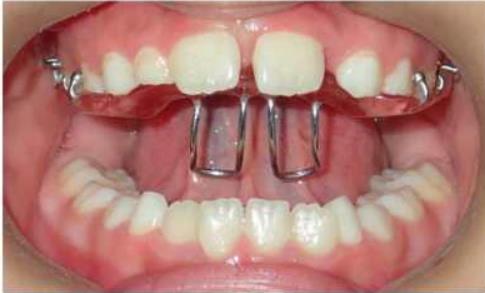

① 合垫舌簧矫治器

矫治方法:前牙反合的患儿往往伴有咬上唇、伸下巴、口呼吸等不良习惯。因此,应首先纠正其不良习惯。口呼吸习惯应进行耳鼻喉科会诊处理,检查其是否伴有鼻咽部疾病,排除鼻咽部疾病后,再进行纠正。对于乳牙列,常用的矫治器为合垫舌簧矫治器;对于混合牙列,常用的矫治器为前方牵引矫治器和FRⅢ矫治器。